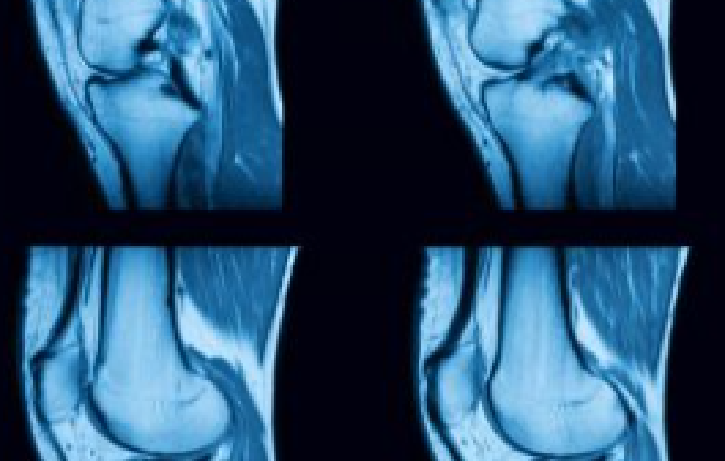

Musculoskeletal Imaging

Focusing on the diagnosis and treatment of the muscles, bones, tendons, and ligaments of the body.Musculoskeletal Imaging

Musculoskeletal (MSK) radiology focuses on the diagnosis and treatment of the muscles, bones, tendons, and ligaments of the body. All of our MSK Radiologists are also board certified by the American Board of Radiology.